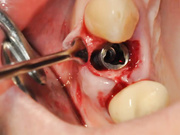

Секреты стоматологии с доктором Самвелом Блея

Категории: Стоматология